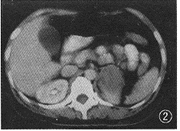

影像学检查:B超示左侧肾上极处实性包块回声,有包膜回声,包膜回声尚光滑,内部回声光点分布欠均匀伴有部分无回声区,深吸气时肾与肿块有移位现象,双肾轮廓清晰,包膜回声光滑,双侧肾皮质光点分布均匀,双侧肾盂光带未见明显分离。B超诊断:腹膜后实性肿物(左侧肾上腺占位性病变)。CT检查:平扫示左侧肾上腺区软组织密度团块影,约4.7 cm×5.3 cm大小,边缘清楚,密度不均(其中可见小低密度区)。左侧肾上腺形态消失。左侧膈肌脚受压向内侧移位(图1)。右侧肾上腺未见异常。增强后该肿物有强化改变,与左侧肾上极相关连,且对左侧肾上极形成弧形压迫(图2)。增强前后腹腔内未见增大的淋巴结影,增强前后肝、胆、胰、脾未见异常。CT诊断:左侧肾上腺区肿物。

图1 CT平扫示左侧肾上腺区软组织密度团块影,约4.7 cm×5.3 cm大小,边缘清楚,密度不均(其中可见小低密度区)。左侧肾上腺形态消失。左侧膈肌脚受压向内侧移位。右侧肾上腺未见异常

图2 增强后该肿物有强化改变,与左侧肾上极相关联,并对左侧肾上极形成弧形压迫